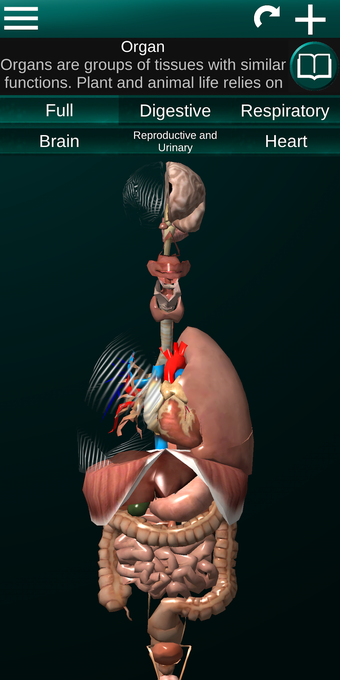

此应用程序显示人体器官的三维模型和所有器官的描述。

您可以触摸每个器官,如心脏、大脑、肺、生殖系统、肝脏、肠道、卵巢、睾丸、胃、肾脏等。

它对所有人都有用,甚至对学生也有用,因为每个解剖器官都以不同的颜色显示。